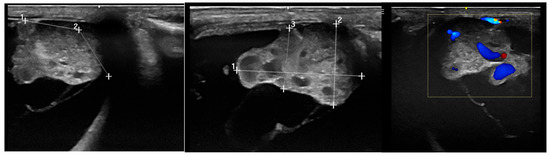

Intraocular Tumors in Horses: Diagnosis, Tumor Classification, Oncologic Assessment and Therapy

Intraocular neoplasia in horses is rare and only few case reports and small case series exist. Intraocular neoplasia has various clinical signs and includes important differential diagnoses in ocular disease. This narrative review of the current literature aims to provide a clinically relevant overview and classification of intraocular tumors in horses and adds a comparative oncological perspective concerning diagnosis, treatment and future considerations. The available clinical and imaging examination techniques allow for a reliable and differentiated investigation of the tumor, even in the standing horse, using high-frequency ultrasound or optical coherence tomography, which have gained importance in equine ophthalmology. Sectional imaging techniques, in particular computed tomography, are suitable for the examination of the peribulbar, retrobulbar and orbital structures. Differentiated diagnostics including precise tumor staging (TNM: tumor, node, metastasis) are essential for a general prognostic and therapeutic assessment. The embryologic and anatomic tissue origin of the neoplasm is the basis for clinicopathologic classification. Medulloepithelioma and uveal melanocytic neoplasia are the most common intraocular tissue formations occurring in horses. Whereas melanocytic neoplasia of the iris can be treated surgically, neuroepithelial tumors regularly lead to bulbus extirpation. Other primary intraocular neoplasms are sporadically reported, as well as intraocular metastasis of systemic neoplasia. Chemotherapy and radiation therapy are not currently used to treat intraocular neoplasia in horses and need to be further investigated, especially regarding the latest developments in human and small animal medicine. In addition, horses and dogs may serve as models for human oncologic research. Full article

Show Figures

Figure 1